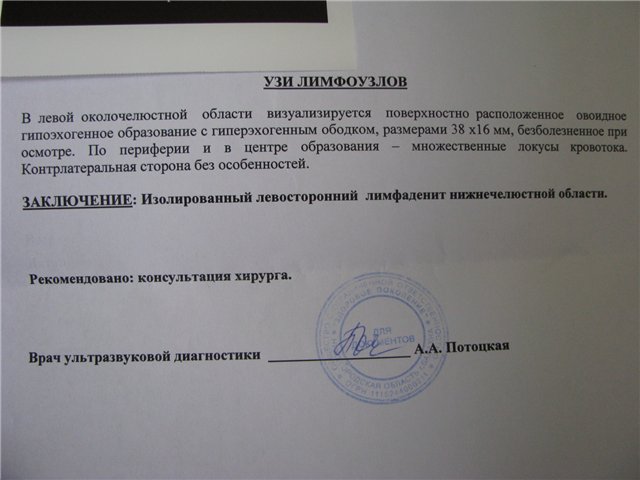

УЗИ лимфоузлов при лимфоме Ходжкина

Раздел: Образы вокруг